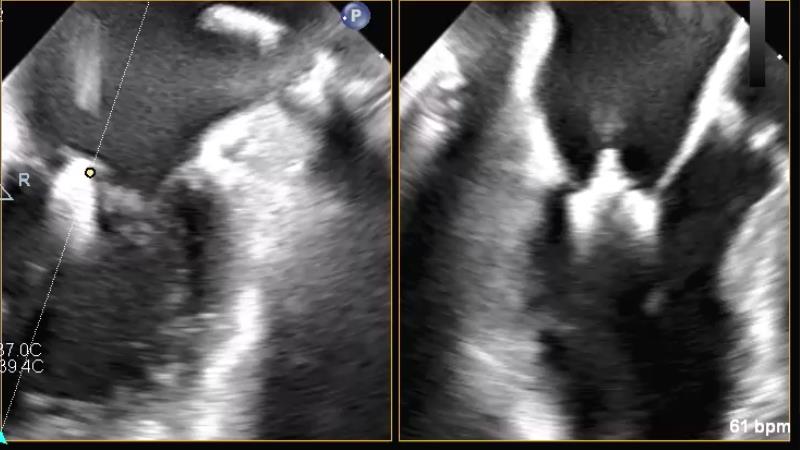

Watch this session to get an overview of a new TEER device, follow the step-by-step procedure related to initial experiences with this device for a Japanese patient with degenerative mitral regurgitation, learn about the latest data from RCT and registries, and follow discussions of challenging TEER cases!

- To learn procedural step-by-step of novel device